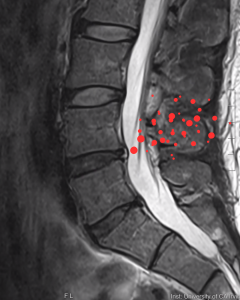

Diagnosis

Herniated Disc

Disc Herniation